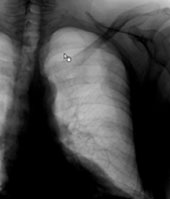

Ein 42-jähriger Freizeitsportler stürzte vor einigen Tagen bei einer Velotour auf die linke Flanke und kommt nun in Ihre Praxis wegen persistierenden thorakalen Schmerzen, v.a. bei tiefer Inspiration.

Sie veranlassen ein Thoraxröntgen, dessen Aufnahmen Sie hier sehen: